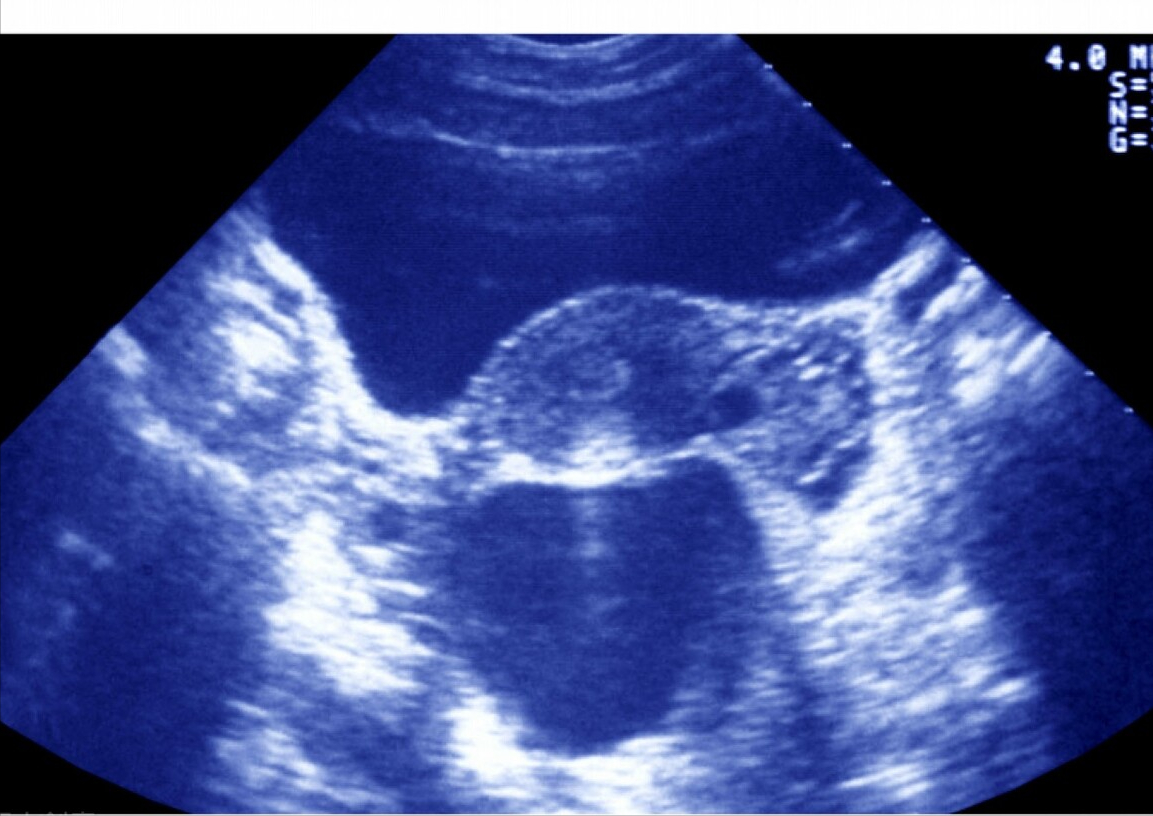

(一)返流型:这种类型的输卵管积水通常量比较多,阴道超声表现为积水量多,患者在排卵期经常会有阴道水样分泌物流出,就要警惕输卵管积水经常返流入宫腔并从阴道流出。这种返流是严重影响胚胎着床的。即使胚胎移植前1-2天抽出来,但经常还是有少量残留,即使一点点的残留积水也会返流入宫腔,对胚胎着床产生不利的影响。表现为反复着床失败。

(二)不返流型:有的患者存在输卵管积水,但是积水量通常不大,而且处于静态不增加的状态,积水也不会返流进入宫腔。这类患者在取卵的时候同时抽吸输卵管积水,然后进行新鲜胚胎移植,还是有一定的临床妊娠率。

这个问题临床上还真是比较难以界定。可以根据患者自己的症状,比如两次月经中期,阴道内经常有水样分泌物流出、而不返流型基本没有太多水样分泌物。返流型积水通常在促排卵期间,随着卵泡的生长而增加,接近取卵时积水会增多,而不返流型,通常量少,而且量没有什么变化,一般不会增多。

有的时候,确实分不清到底是返流型还是不返流型。不返流型积水,因为量不大,即使取卵时不抽吸,部分患者新鲜周期移植并没有影响胚胎着床率。而积水量大的患者通常被建议采用冻胚移植,而且移植前1-2天抽吸输卵管的积水。反复移植失败的病人还是建议做腹腔镜下输卵管结扎术。